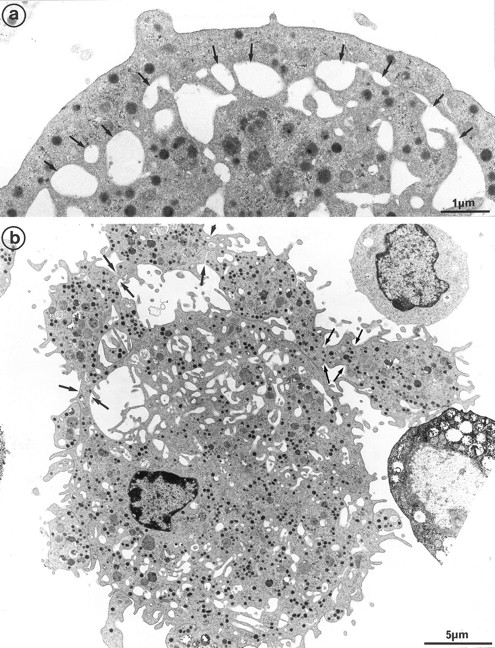

Interestingly, platelet-producing MKs were surrounded by numerous microparticles from 0.1 to 0.3 μm in diameter (Fig 7a). It is conceivable that the particles might be transverse sections of cell surface–connected pseudopods. However, they were also scattered in the vicinity of smooth areas of the plasma membrane and present along dilated channels of demarcation membrane with a smooth surface. These areas were devoid of pseudopods that could have been transversely sectioned. Moreover, these particles were not observed in the vicinity of thrombin-activated MKs, the surface of which was bristled with numerous long and thin pseudopods29 (Fig 7b). Some of these particles seemed to arise from fragments of the MK elongated arms, located between constriction zones, which were not included in the newborn platelet and were thus released into the surroundings. By immunoelectron microscopy, GpIIb-IIIa was also found to be strongly expressed on the shed microparticles.

(a) MK grown for 7 days from CD34+CD38+ progenitors in the presence of Mpl-l: numerous microparticles (arrows) surround this platelet-shedding mature MK. (b) Cultured MK having undergone thrombin activation (1 U/mL for 5 min): the plasma membrane is bristled with numerous pseudopods (p). However, unlike platelet-shedding MKs, only a few microparticle profiles are seen around the cell surface (arrows), probably corresponding to some pseudopod transverse sections.